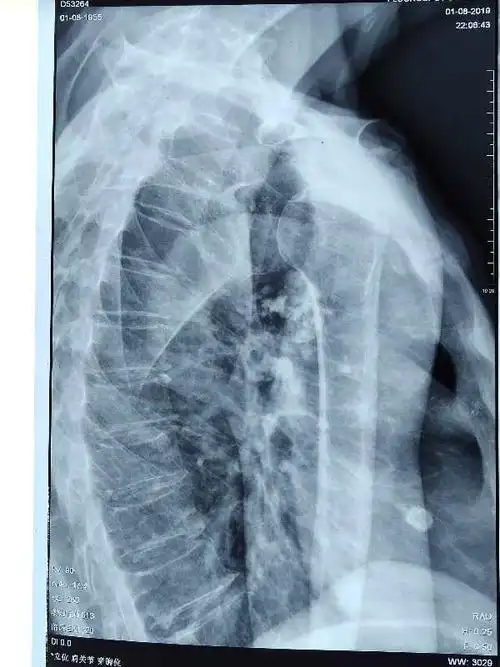

肩关节的摄影体位

肩关节x线检查体位大全

a-h间距测量值为x线图像中测得的肱骨头顶与肩峰端前外下角之间的垂直

x线从患者背后穿透,患者前胸紧贴探测平板,双手背于髂骨上,肩部下垂